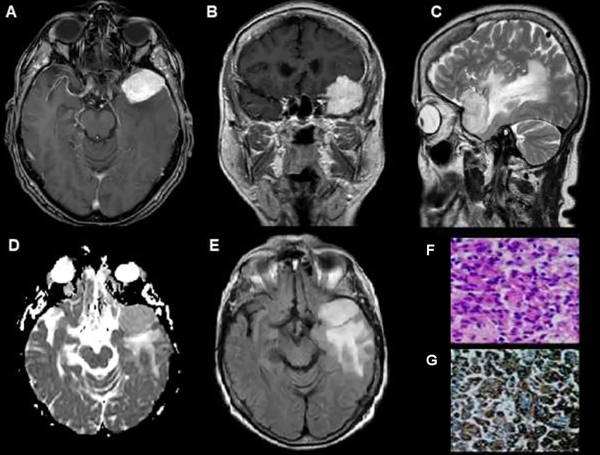

Figura 1. Meningioma del ala del esfenoides, grado I OMS. (A) RM axial T1 con Gd: lesión con captación hiperintensa y homogénea (flecha). (B) RM axial T1. (C) RM sagital T2: edema perilesional de aspecto hiperintenso (flecha). (D) Mapa de ADC: Comportamiento hiperintenso con aumento de intensidad (flecha). (E) RM FLAIR axial con captación hiperintensa de edema perilesional. (F y G) Microscopía: Proliferación compuesta por células de citoplasma amplio y núcleo redondeado u oval con pseudoinclusiones. Se observa abundante cantidad de vasos dilatados regulares.